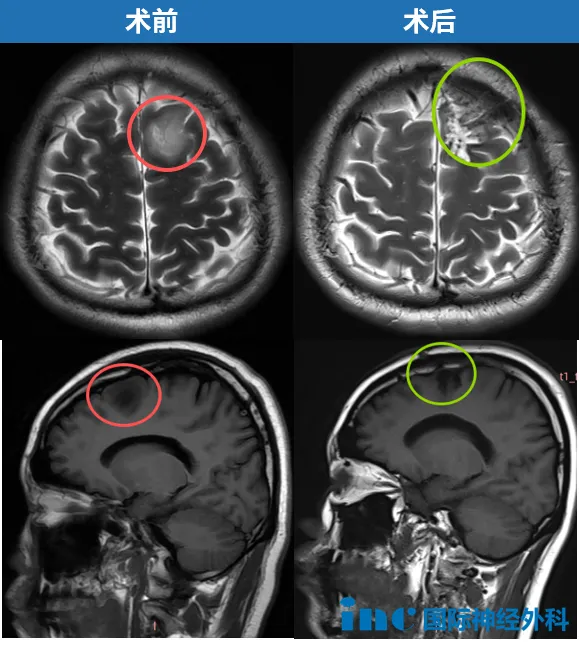

2025年,申先生在例行体检中意外发现胶质瘤。当时他并未出现任何临床症状,但仍果断接受了开颅手术。手术实现了肿瘤的扩大切除,术后病理学检查结果确认为WHO 2级少突胶质细胞瘤。面对深爱的家人,这次劫后余生的经历让他对人生规划产生了新的思考。他决定将更多时间用于陪伴家人,同时迎接新生命的到来,用心享受美好的生活。

决策既定,便迅速执行。2025年9月,申先生在首都医科大学附属北京天坛医院国际部由巴特朗菲教授亲自主刀接受了手术。手术结果十分理想:肿瘤得以扩大全切(扩大3-5毫米),病理诊断为WHO 2级少突胶质细胞瘤,预后极佳。更让家属欣慰的是,术后申先生无需进入ICU,当天即恢复意识,肢体活动、语言功能都保持正常。